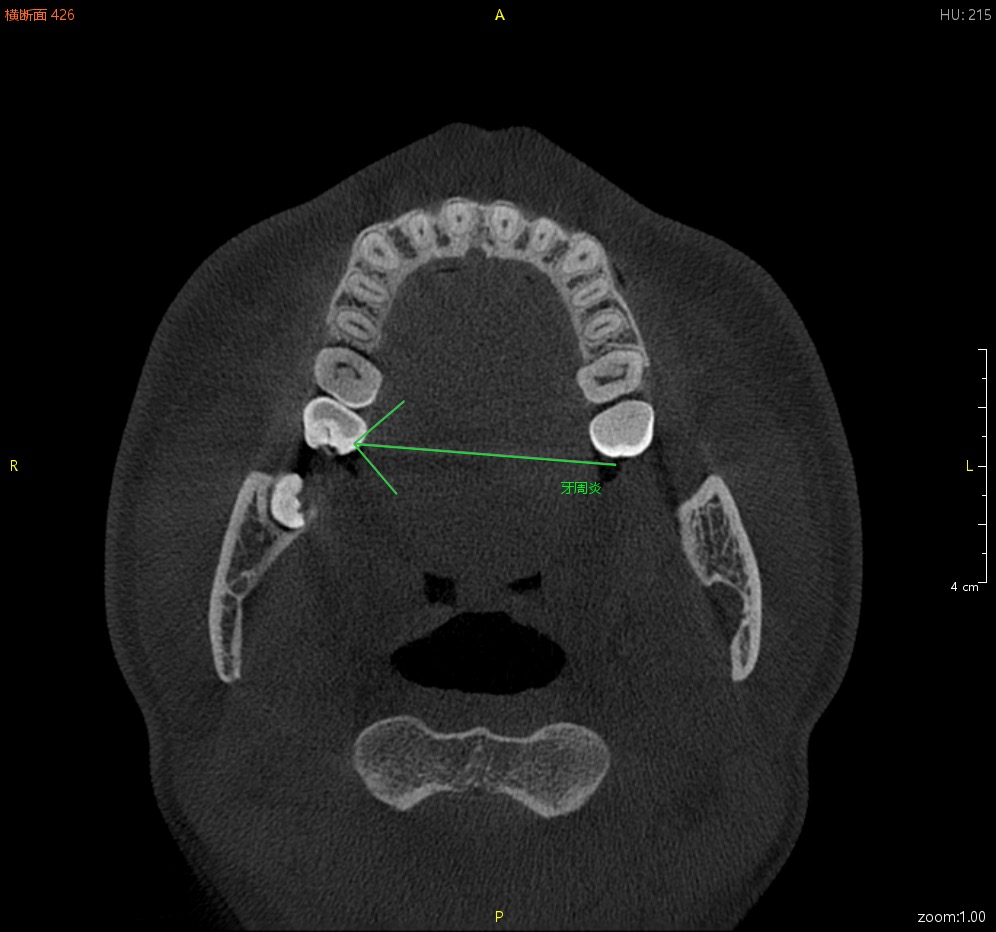

箭头与注释工具

直线测量 折线测量 曲线测量 角度测量 区域测量 骨密度测量 箭头与注释工具